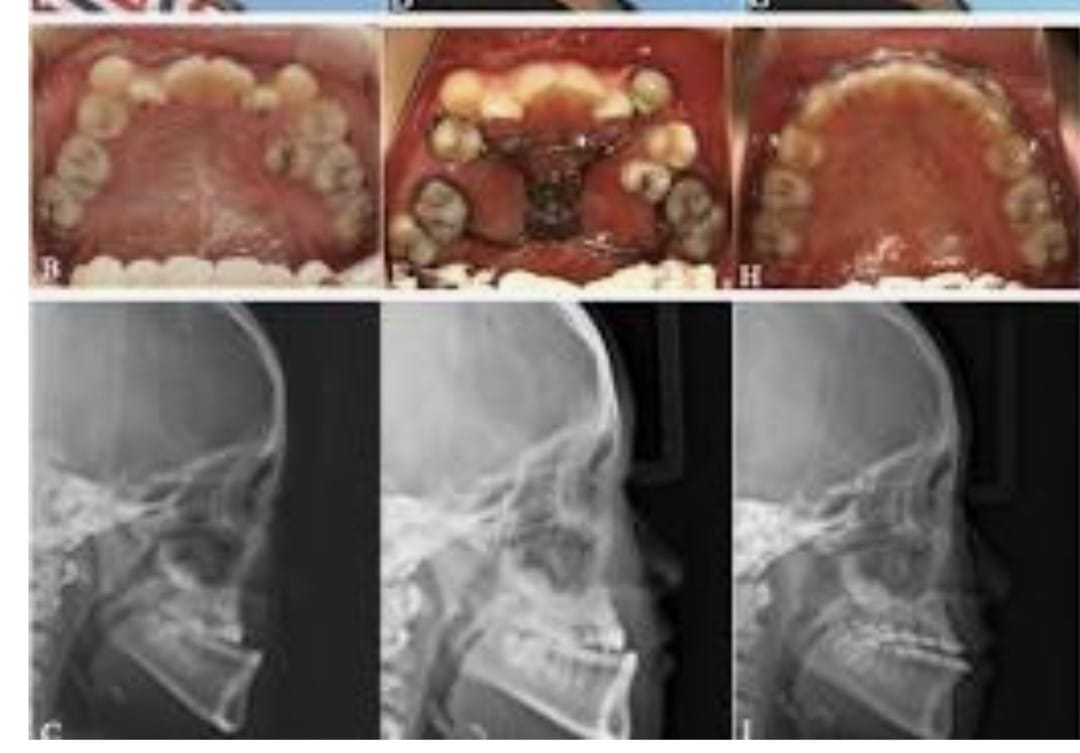

Maxillary hypoplasia is a condition characterized by the underdevelopment of the upper jaw (maxilla), which can affect both facial appearance and oral function. It often results in a sunken midface, improper bite alignment, and may contribute to breathing or speech difficulties. This condition can be congenital or develop during growth, impacting overall facial harmony and balance.

Treatment for maxillary hypoplasia focuses on correcting the position and structure of the upper jaw to improve both function and aesthetics. Depending on the severity, procedures such as orthognathic (jaw) surgery are performed to reposition the maxilla, enhance facial profile, and achieve proper bite alignment. With advanced surgical planning and modern techniques, patients can achieve improved facial balance, better oral function, and long-lasting results.

- Pre-surgical Orthodontics: Often needed before the actual surgery takes place. Imaging: X-rays and CT scans are required.

- Planning: Virtual surgical planning is performed on a computer, along with model surgery.